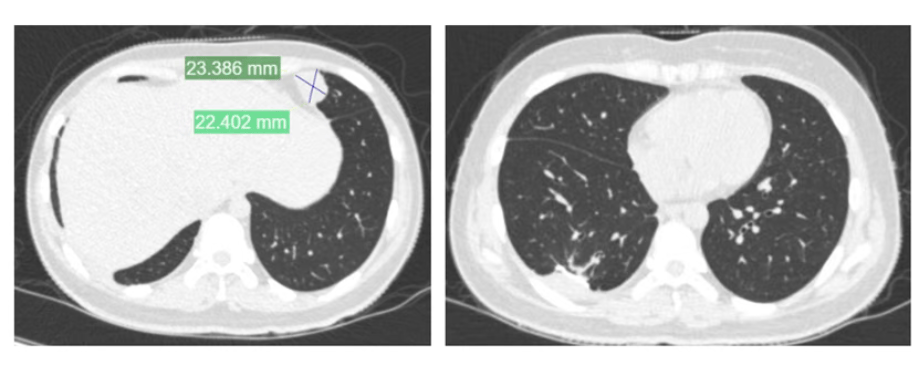

夏夏前期接受了术前化疗、截肢手术及术后化疗,使用的是一线化疗方案皇冠信用盘代理 。然而,结疗不到一年,肺部出现转移病灶,经过手术切除后未再进行化疗。术后5个月,左肺再次发现新发转移病灶。

2024年11月,夏夏接受胸腔镜下右肺下叶切除术皇冠信用盘代理 。2025年1月复查:右肺术后改变。